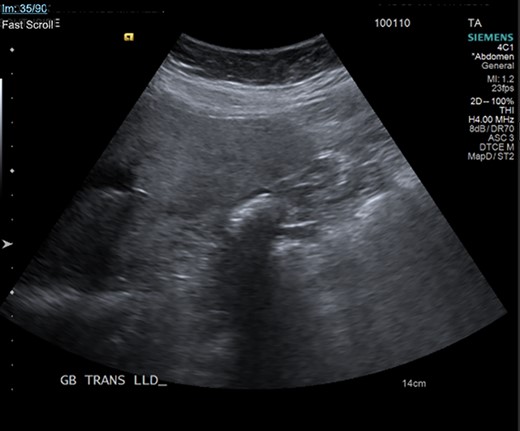

Gallbladder agenesis is a rare anomaly in which an individual is born without a gallbladder. This phenomenon affects <0.1% of the population with only 400 cases documented in medical literature to this day [2, 3]. This anomaly is discovered incidentally during workups for symptoms consisting of gallbladder pathology as seen in our patient. Initial work up for a gallbladder pathology includes a right upper quadrant ultrasound and, in this patient, it showed a collapsed gallbladder around gallstones, as seen in Fig. 4. This pointed to a diagnosis of cholecystitis. A further look with a HIDA scan confirmed this diagnosis as it showed the absence of radiotracer entering the gallbladder even after the administration of morphine, seen in Figs 5 and 6. A non-visualized gallbladder typically occurs due a gallstone obstructing the passage of the radiotracer entering the gallbladder [4]. Gallbladder agenesis could cause this radiographic finding as well, however, this anomaly was low in our differential as the initial ultrasound showed a collapsed gallbladder and the patient’s absence of other medical conditions associated with gallbladder agenesis, such as Klippel–Feil syndrome, horseshoe kidney, malrotation of the gut or aberrant left pulmonary artery, none of which were suspected in our patient seen on examination and radiographically [1]. The normal location of the gallbladder is located on the undersurface of the liver, aligning with the intrahepatic line that separates the right and left hepatic lobe. There was no sign of this organ once the liver was elevated, seen in Fig. 1. The likely cause of this patient’s chronic right sided abdominal pain were the multiple abdominal adhesions, which were lysed.

Ultrasound of the gallbladder showing echogenic shadow from the gallbladder fossa around gallstones, suggesting a collapsed gallbladder around stones.